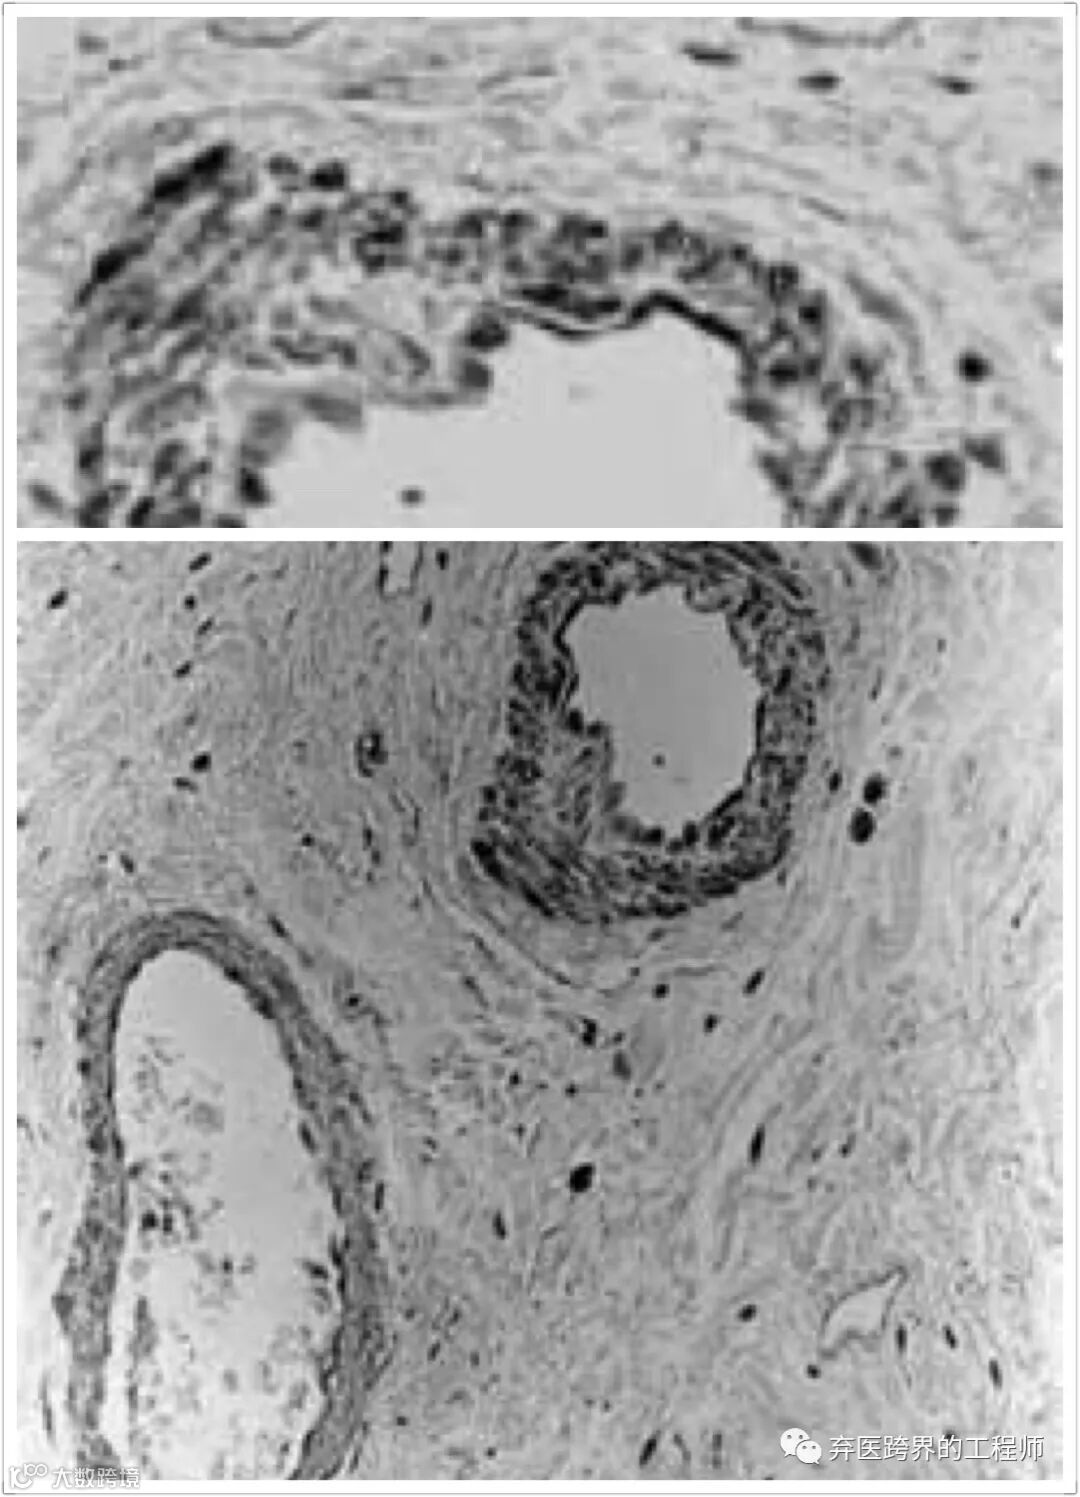

好,说回刚刚的话题,科学家们想知道这些黑色的鸡到底为什么是黑色的。他们首先在一些野生的鸟类身上发现一个情况,这些鸟类和同类相比,羽毛和眼睛的颜色更深,偏向于棕色和烟灰色。等这些鸟死去以后,解剖它们的身体发现,它们的内脏表面也是接近黑色的。科学家给这种情况起了一个名字,叫“纤维色素增生”。“纤维色素增生”这个定义有点儿复杂,我来给你解释一下,纤维的绞丝旁,意味着这个东西跟线有关,纤维其实就是丝线状的东西,可以联结成片地包裹在其他东西的外面。比如包裹在我们内脏的外面。色素,是让事物呈现颜色的东西。增生就是增加,原先没有的,现在多出来了就叫增生。这几个词连在一起, “纤维色素增生”就是说包裹在内脏外面的纤维类的东西突然增加了很多颜色。

科学家发现,这种 纤维色素增生的现象,是一种基因变异造成的。这个变异引导色素细胞进入了身体内部,在内脏表面的纤维上沉积了下来 。科学家们甚至找到了这个变异的源头,其实是因为一小段基因出了问题。但让人失望的是,这个变异只是导致它们的内脏变黑,不会导致羽毛或其他地方变黑。

纤维色素增生导致黑鸡的内脏也是黑的

EDN3基因参与了对产生黑色素的黑素细胞的调节